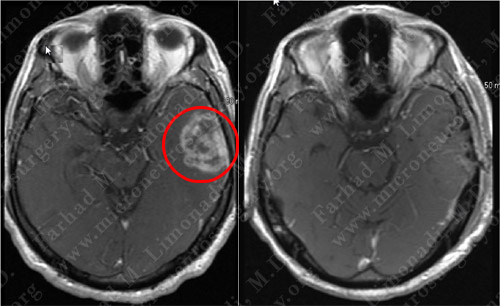

Post-Op Imaging

Post-op MRI shows complete resection of the tumor with no injury to surrounding neurovascular structures.